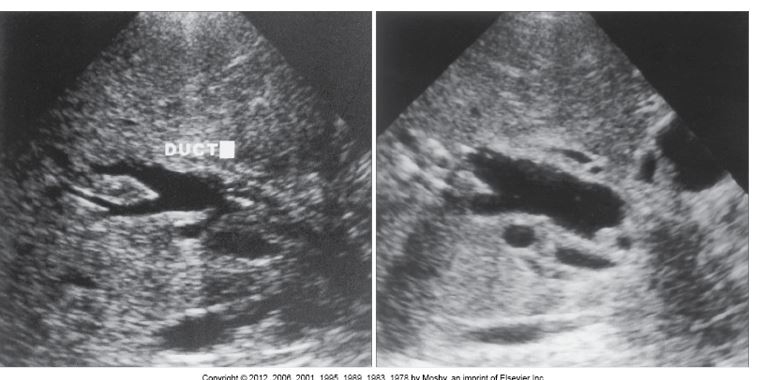

arrow: MLF

curved arrow: portal vein

arrow: CBD

curved arrow: CBD

arrow: HA

On this sagittal image, the hepatic artery (HA) is shown anterior to the common duct (CD)